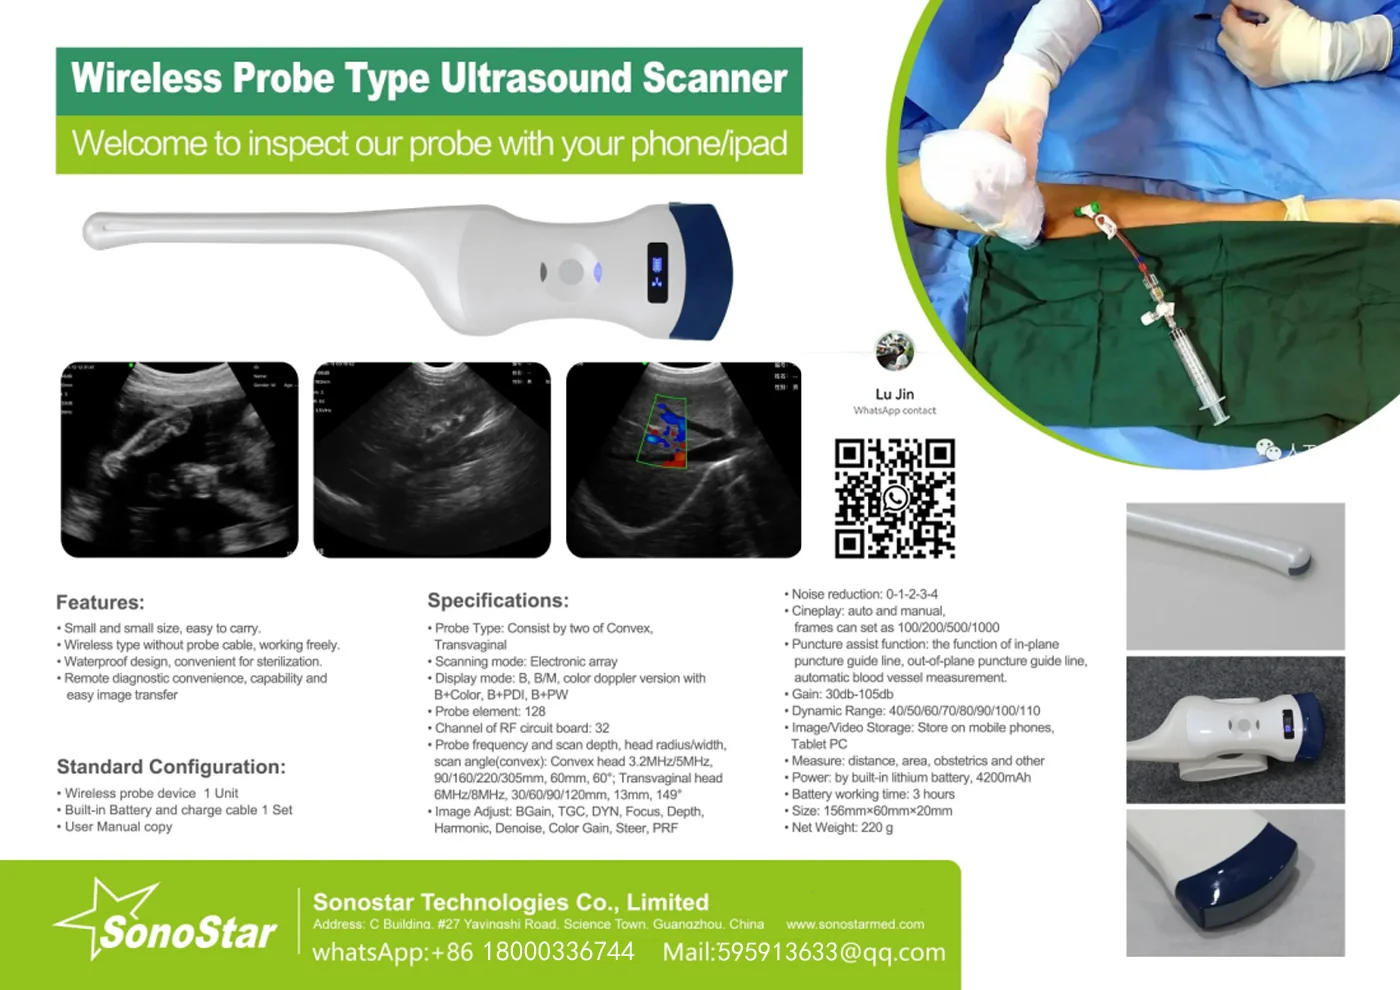

Convex Probe Pictures:

This machine can be used for both humans and animals: